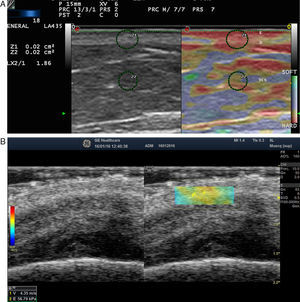

Elastography of Normal Skin and AdnexaThe stiffness of healthy skin varies according to the cutaneous layer being studied. The dermis is more rigid than the subcutaneous cellular tissue16 (Fig. 2, A, B). In the subcutaneous cellular tissue, the septa are more rigid than the fat lobules. Blood vessels, like the peripheral nerves, are not very rigid in comparison to the surrounding subcutaneous cellular tissue.16

A, Strain elastography of normal skin. Note the strain ratio of the dermis and the fat (SR=1.86), which indicates that the dermis is stiffer than the subcutaneous tissue.

E indicates epidermis; D, dermis; TCS, subcutaneous cellular tissue.

B, Shear wave elastography of the dermis of the scalp. In the lower right corner, note the parameters of velocity and pressure in the region of interest (yellowish-green rectangle).